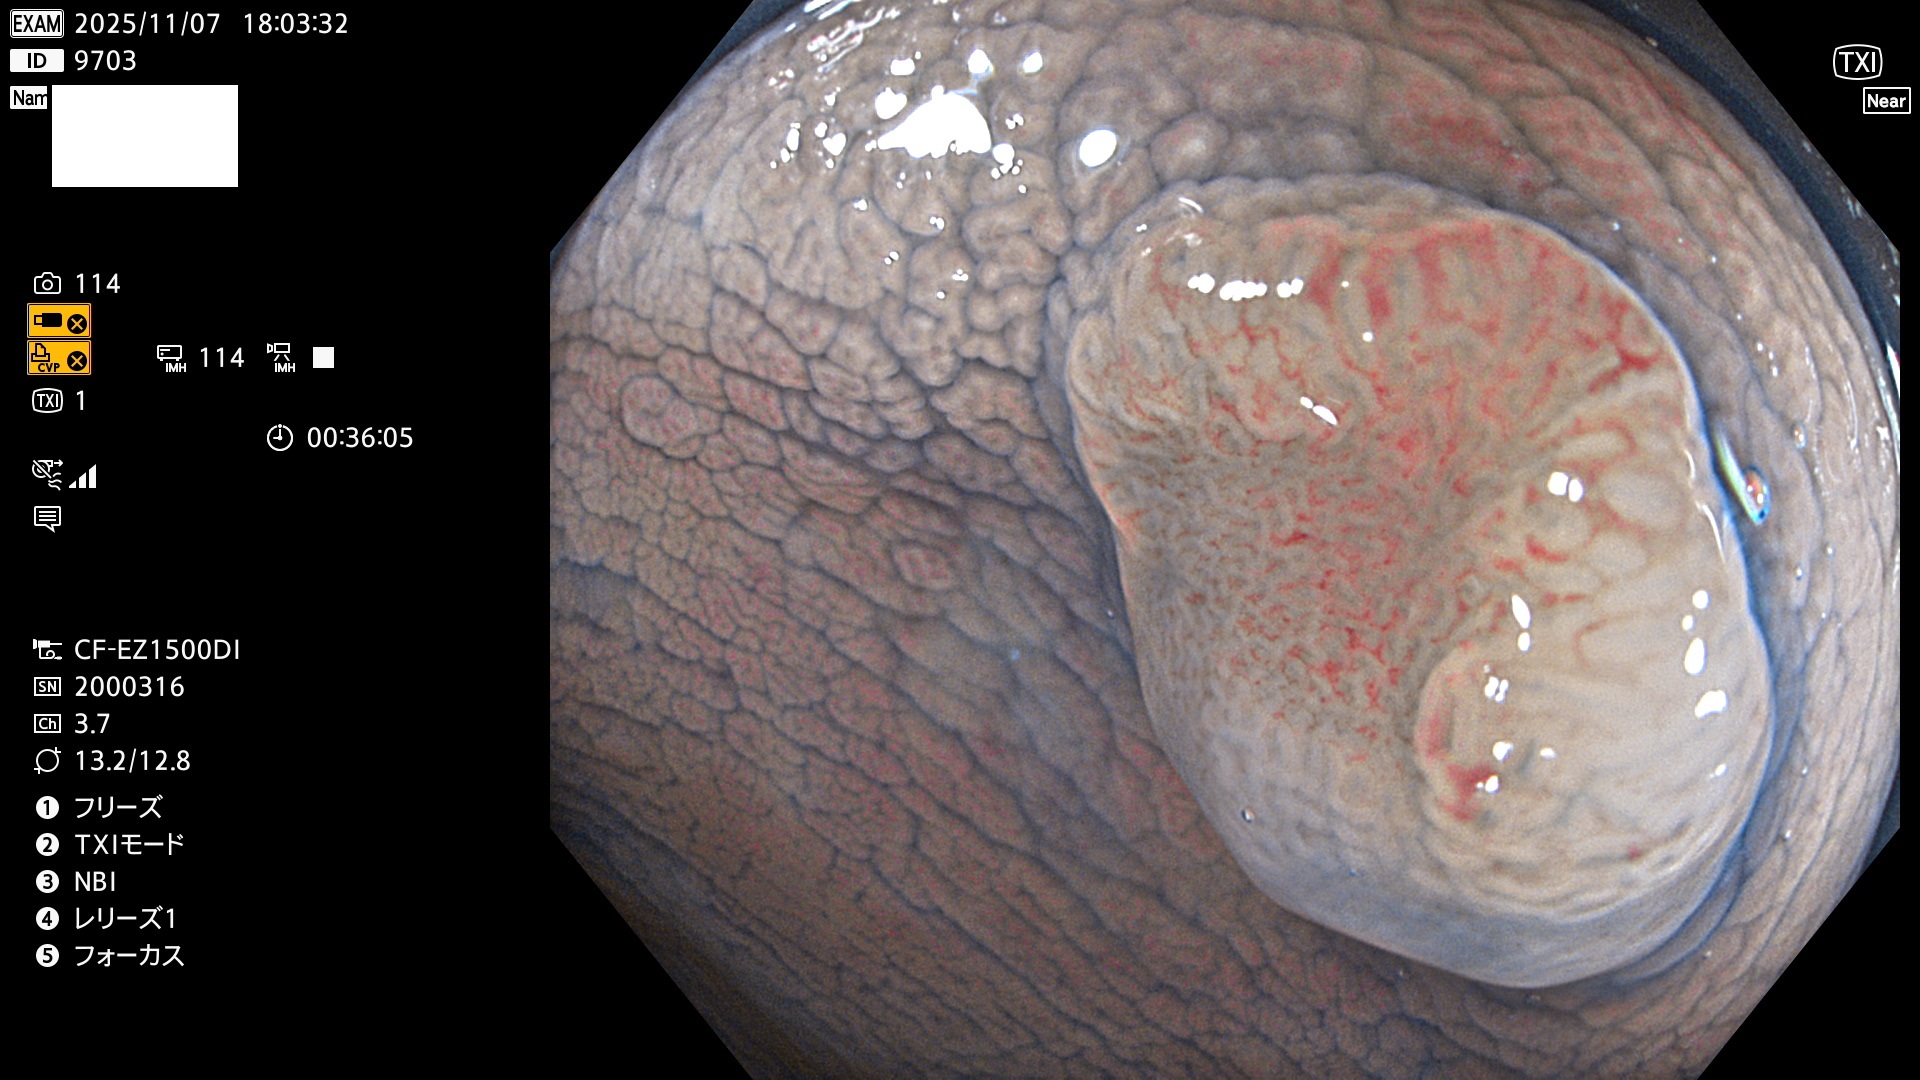

完全に平坦な物をUb、陥凹している物をUcと呼びます。Ubは認識が困難で、Ucはびらん(炎症)と紛らわしいために見落とされやすく、「内視鏡後・大腸癌」の原因になります。

専門的)Uc=De Novo癌? 内視鏡の解像度が低かった時代、このような説もありました。しかし今日の高精度内視鏡では良性の微小なUc型腺腫(APC遺伝子異常の腺腫)が日常的に見つかります。Ucこそが多段階発癌(Adenoma-Carcinoma Sequence)のMain Routeです。

2025年11月6日〜11月9日の4日間(40件)6個 (Uc_ADR=6個/40人=15%)